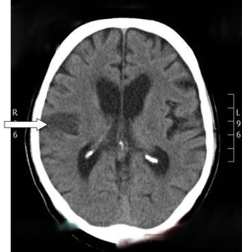

How is haemorrahagic stroke classified?

Primary intracerebral and secondary intracerebral haemorrhage

What are causes of primary intracerebral haemorrhage?

Hypertension and amyloid angiopathy